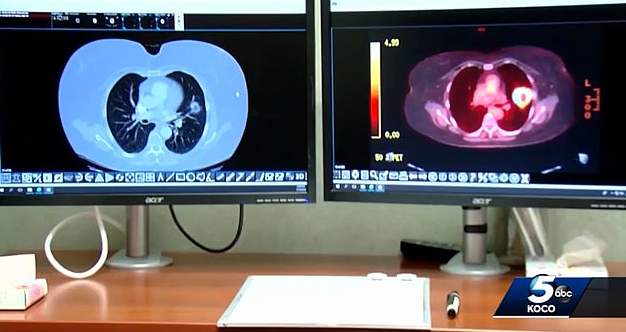

이 영상에 따르면 조 티펜스씨는 2016년 말기 소세포폐암 진단을 받았으며 다음 해 1월 암세포가 간과 췌장, 위 등에 퍼져 3개월 시한부라는 이야기를 들었습니다. 이에 한 수의사가 그에게 개 구충제를 복용하고 6주 만에 뇌암이 나은 환자 이야기를 전하며 펜벤다졸 복용을 권했는데요 이후 펜벤다졸을 복용한 티펜스는 3개월 뒤 암세포가 깨끗이 사라졌다고 합니다. 과연 이러한 암의 완치가 대부분의 사람들에게 일어날 수 있을까요?